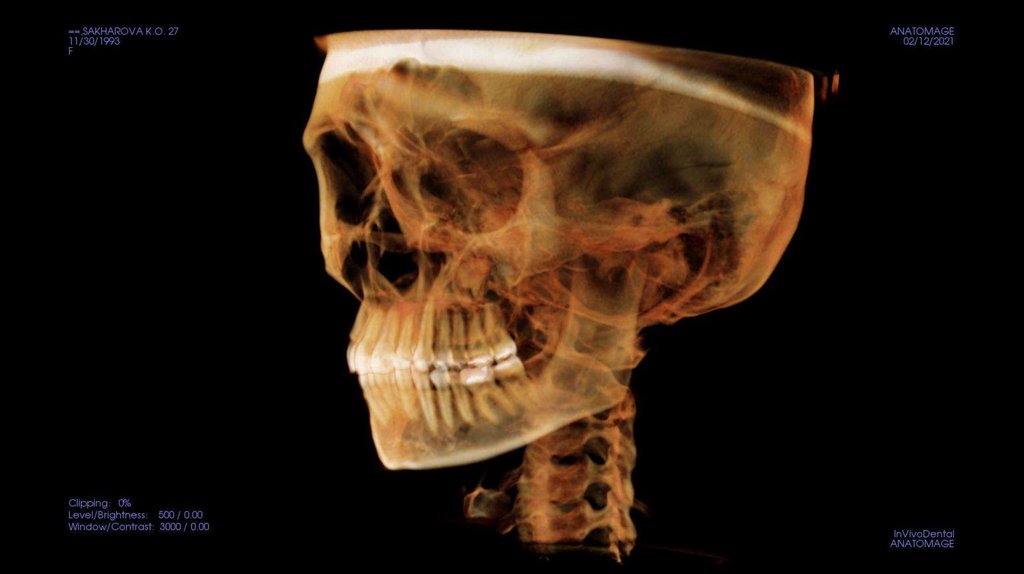

По рассчетам снимков:

• Ретрузия резцов верхней челюсти

• Компрессия головок суставов, особенно правого( началось

ремоделирование)

• Костная ассиметрия(10 мм)

• 2 класс

• 25, 46 зуб – нуждается в санации

• Требуется профессиональняа гигиена полости рта

• Клиновидные дефекты 43, 44

• 18, 28, 38, 48 отсутствуют.